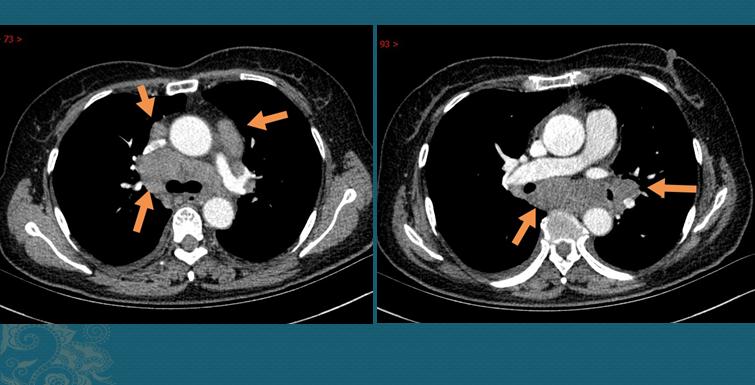

2.一位40多岁的女士,偶尔胸闷、咳嗽,也做了一个CT,发现纵隔多发肿大淋巴结:

病例来自济宁边翠霞医生,致谢

我们知道,淋巴结肿大常见于癌细胞转移,很多小细胞肺癌和低分化腺癌病人,肿瘤发展快,可以在较短的时间内发生纵隔多发淋巴结转移,有些病人在出现症状时就已经是晚期……

1.肺门周围及纵隔多发肿大淋巴结。

这种类型最常见(约占77%),如上图第二位女病人,有时需要与淋巴结结核、恶性肿瘤鉴别;

1.胸部CT发现对肺门及纵隔淋巴结对称性肿大(增强CT呈均匀强化),伴或不伴肺内多发网格状、斑片状、结节状影;